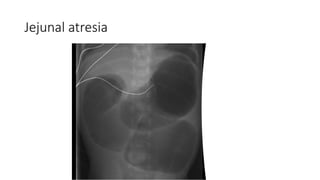

• Double bubble sign – duodenal atresia

• Tripple bubble sign – jejunal atresia

Jejunal atresia

INVESTIGATION • Radiological 1. Plainx-rays of abdomen Supine view: gaseous dilated bowel loops. Small intestine: dilated bowel is central, valvulae conniventes seen. Colon: dilated bowel is in the flank, haustration. Erect view: multiple air fluid levels, absent gas shadow in the pelvis. • Double bubble sign – duodenal atresia • Tripple bubble sign – jejunal atresia 2. Abdominal CT scan/ CT colonography 3. E/U/Cr 4. Full Blood Count 5. Urinalysis 6. Contrast Study 7. Chest Xray 8. ABG (Metabolic acidosis in low obstruction and metabolic alkalosis is high obstruction).